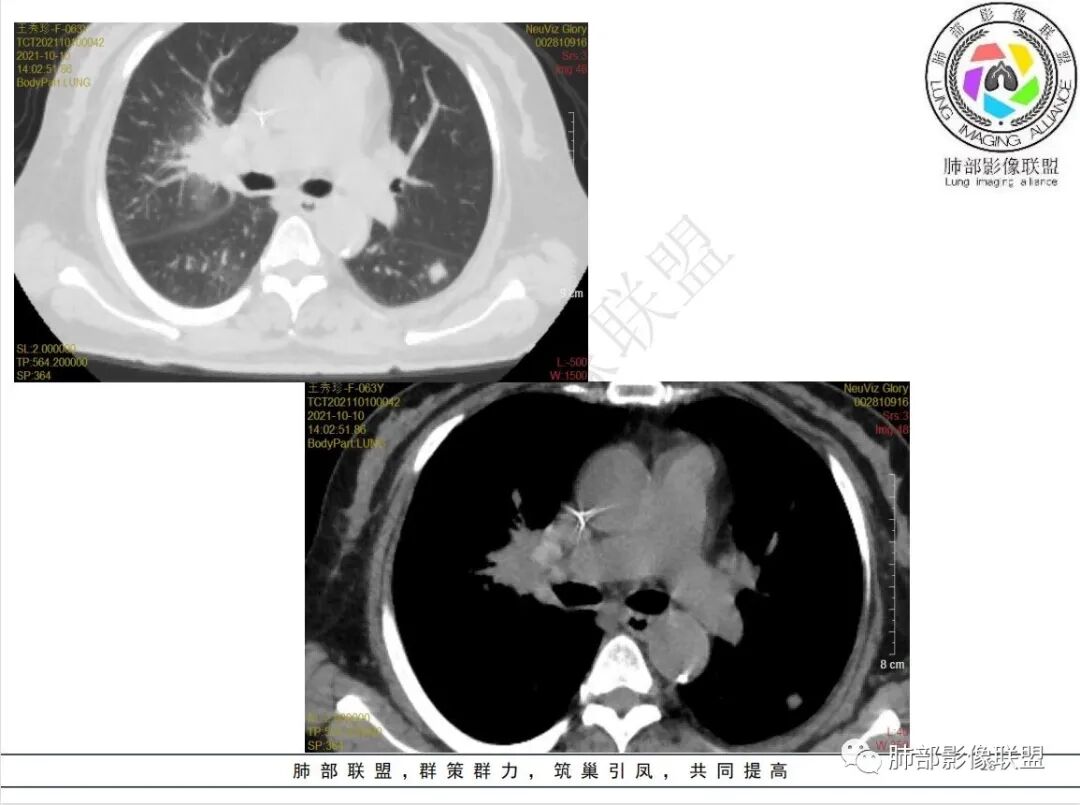

白血病化疗后,出现多发结节,边缘可见晕征,病灶内可见多发坏死,右肺中叶肺动脉可见充盈缺损,右肺中叶可见融冰征,考虑毛霉菌,右肺中叶肺动脉栓塞伴右肺中叶肺梗死。

4.白血病化疗后,CT上出现多发结节,边缘可见晕征,病灶内可见多发坏死,右肺中叶肺动脉可见充盈缺损,右肺中叶可见融冰征,右肺中叶肺动脉侵犯栓塞伴右肺中叶肺梗死,可符合真菌感染。

血管侵袭性曲霉病是最常见的类型,其特征是真菌菌丝侵入和阻塞中小肺动脉,形成凝固性坏死、肺泡出血或出血性梗死。

6.肺曲霉病典型的CT表现是结节周围有磨玻璃样的晕征表现,或胸膜为宽基底的楔形实变。晕征表现为曲菌感染的肺结节伴梗死和凝固性坏死,周围有肺泡出血。最终可出现空泡征象,并可观察到中央坏死组织与周围肺实质分离形成空气新月征。

晕征已被认为是侵袭性曲菌病的早期征象之一。